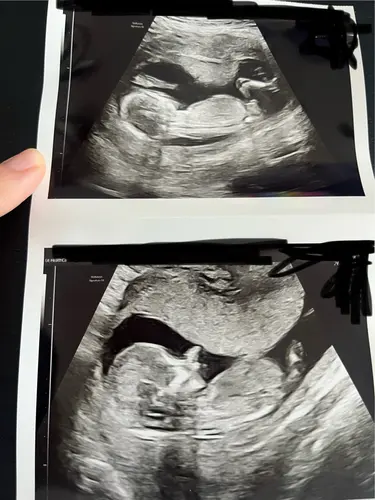

Heel benieuwd of jullie het kunnen zien aan de hand van nub.. Ik ben er niet goed in namelijk :))